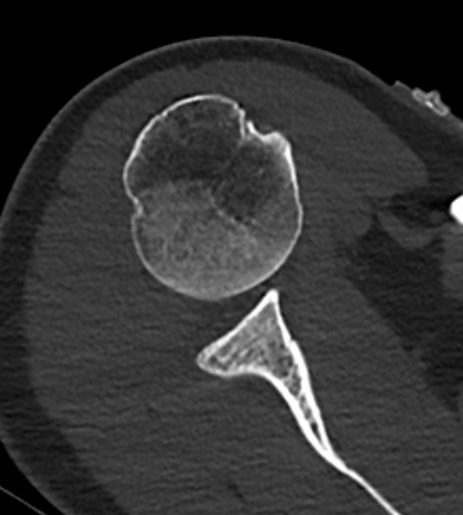

CT / MRI

Xray

Traction xray

- patient standing with 5-10 kg in each hand

- inferior subluxation of head